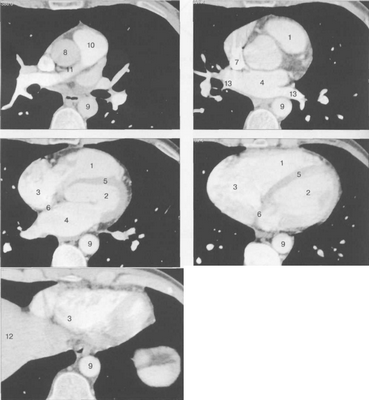

Рис. 9.34. КТ сердца и сосудов.

1 — правый желудочек; 2 — левый желудочек; 3 — правое предсердие; 4 — левое предсердие; 5 — межжелудочковая перегородка; 6 — межпредсердная перегородка; 7 — верхняя полая вена; 8 — восходящая часть аорты; 9 — нисходящая часть аорты; 10 — легочный ствол; 11 — правая легочная артерия; 12 — диафрагма; 13 — легочные вены.